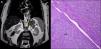

A multiphase computerised axial tomography scan (CT scan) of the abdomen was performed, which showed a liver graft of normal size and morphology, and a nodule measuring 4mm in liver segment VI with contrast uptake in the arterial phase and no evidence of washout in the venous phase, LI-RADS-3. A lobulated, solid, left adrenal mass measuring 77×44mm was also described. Three months later, magnetic resonance imaging (MRI) of the abdomen showed enlargement of the adrenal lesion (88×66mm) (Fig. 1A), which was not characterisable with this imaging method, and stability of the liver lesion. The presence of hormone hypersecretion was ruled out: thyroid function tests, cortisol, ACTH, DHEA, 17-OH progesterone, urine catecholamines and cortisol suppression following dexamethasone injection were all within the normal range. It was decided that it was best to surgically remove the lesion. Histopathology tests (Fig. 1B) revealed a metastatic carcinoma with an immunohistochemical morphology and profile consistent with hepatocellular carcinoma (Hep Par-1, cytoplasmic TTF-1, CAM 5.2 and CD10). There was no infiltration of the resection margins. The size of the liver lesion had remained stable on the control CT scan. A PET/CT scan was performed, which showed no suspicious malignant lesions. Today, five months after surgical resection, the patient is stable and shows no signs of tumour recurrence on imaging scans, with alpha-fetoprotein levels of 6.7IU/ml.